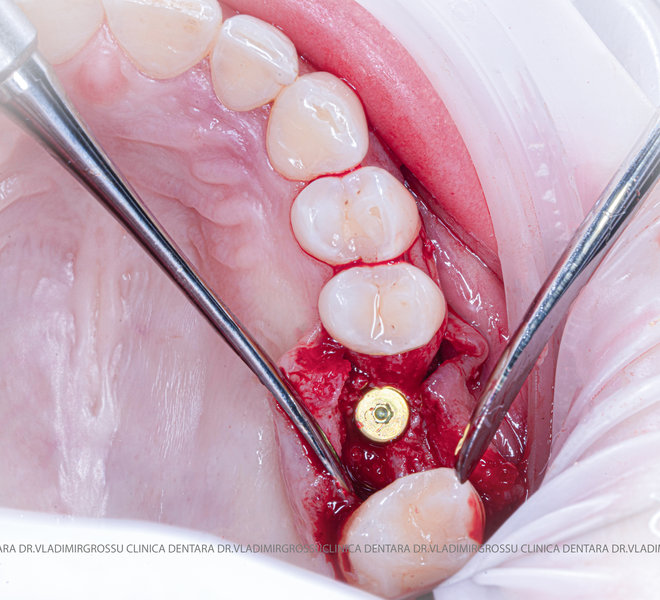

Stomatologia estetică reprezintă în prezent una dintre direcțiile principale de specializare a medicilor clinicii Dr. Grossu din Chișinău.Adiția sau augmentarea osoasă este o procedură chirurgicală prin care se refac defectele osoase rezultate în urma extracțiilor dentare, bolii parodontale sau traumelor dento-alveolare.

După extracția dentară, în intervalul de 6-12 luni, osul alveolar suferă un proces natural de remodelare, ceea ce conduce la scăderea volumului osos prin rezorbție. De aceea, inserția implantului dentar este ideală imediat după extracție sau, cel târziu, în primele 3-4 luni după aceasta.Scopul procedurilor de adiție osoasă este refacerea fundației osoase necesare pentru stabilizarea corectă a implantului dentar. Pentru ca un implant să reziste în timp la forțele masticatorii, este nevoie de o bază osoasă solidă și sănătoasă.

Un element esențial în procedura de aditie osoasă este utilizarea membranelor biologice, care izolează materialul osos de țesuturile moi (gingie) pe durata procesului de vindecare. Cele mai recomandate sunt membranele resorbabile din colagen sau pericard.